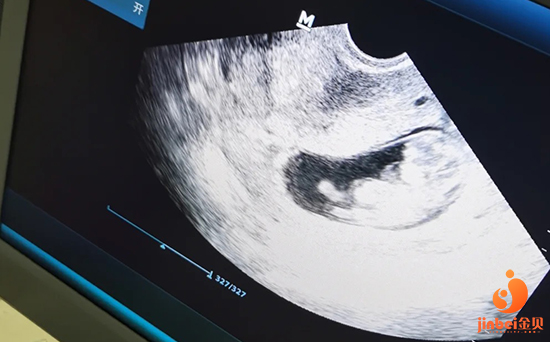

预测排卵:主要是B超监测卵泡的发育程度,以确定给予激素诱发排卵的最佳时间。

预测排卵:要取排卵前成熟的卵子,首先要确定排卵期。主要是B超监测卵泡的发育程度,以确定给予激素诱发排卵的最佳时间。